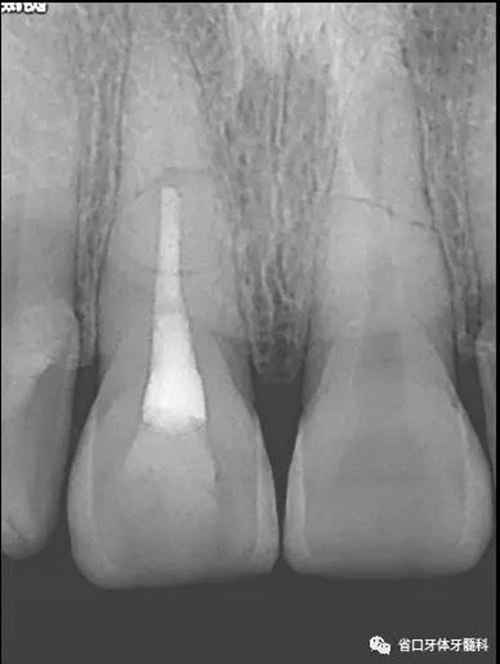

X線片:11、21根中段見橫行根折線,無移位,根尖無明顯異常。

圖2 術前根尖片

處理:11橡皮障隔濕,顯微鏡下開髓,揭髓室頂,K銼疏通根管,拔髓,測長度(到根折斷端處)17mm,顯微鏡下鎳鈦預備根管,按工作長度預備根管至60#,沖洗根管,吸干,顯微鏡下MTA斷端封閉,髓腔內(nèi)放置半飽和蒸餾水棉球一個,玻璃離子臨時充填。

圖6 斷端MTA封閉術后